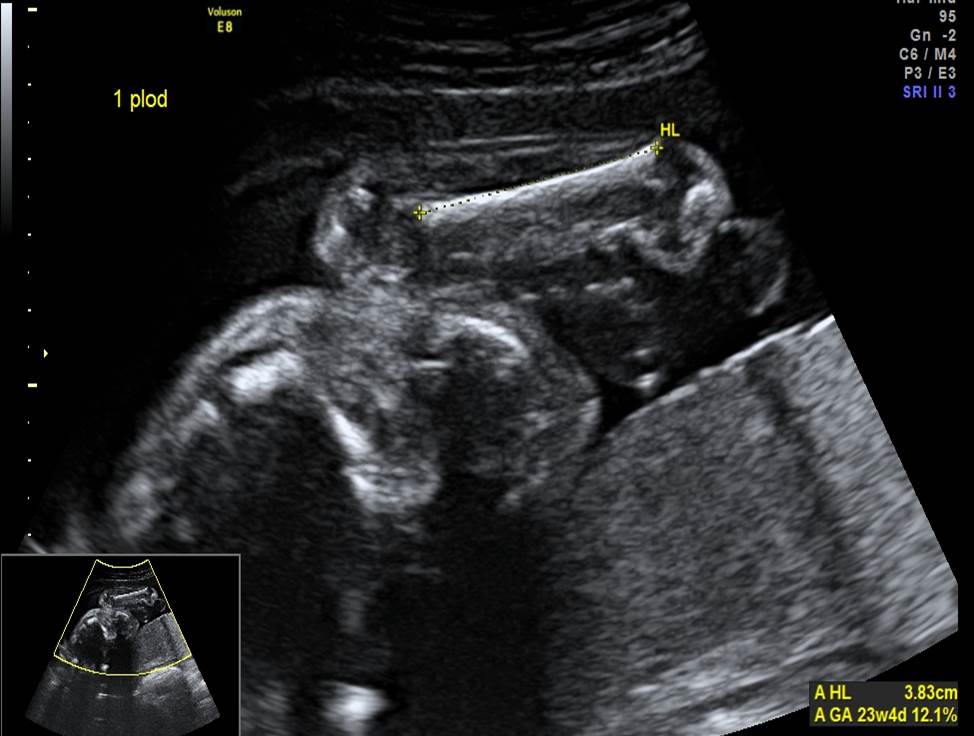

Проанализируйте изображения первого плода из дихориальной двойни в 24 недели (плод мужского пола), установите диагноз и дальнейшую тактику ведения беременности